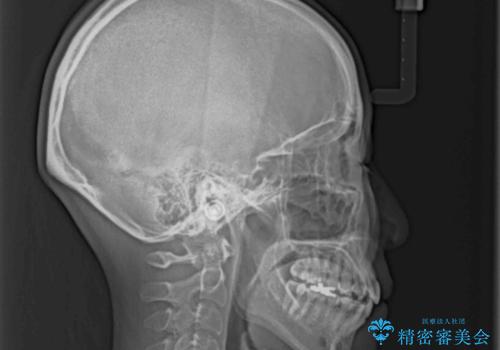

- 上下の八重歯を気にして来院された患者様です。

八重歯の後ろの歯を1歯抜歯し、補助装置(リンガルアーチ)を用いて八重歯の位置を改善し、その後インビザラインにより矯正治療を行うこととしました。

右側のみ上下小臼歯を抜歯したため、上下の正中が右にずれてしまう可能性があります。

また、元々右側は上下が咬み合っていないため、矯正をしても咬み合わないことも考えられました。

治療期間はかかりましたが、正中も合い、綺麗な仕上がりとなりました。